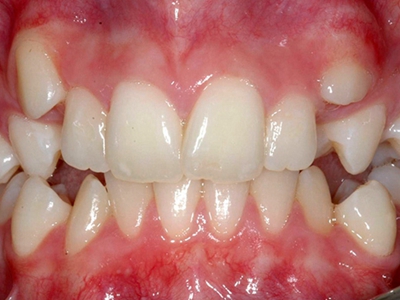

阻生牙是指由于邻牙、骨或软组织的阻碍而只能部分萌出或完全不能萌出,且以后也不能萌出的牙。引起牙阻生的成因,主要是由于颌骨缺乏足够的空间容纳全部恒牙。常见的阻生牙为下颌第三磨牙、上颌第三磨牙及上颌尖牙。

对于阻生牙的处置需要首先明确阻生牙齿发育情况是否正常,对于由于早期外伤或其他原因造成发育异常,如牙根弯曲、短根等情况的阻生牙,还应根据患者的综合情况,决定牙齿是否保留。

发育正常的牙齿同时正畸治疗又不需要进行拔牙矫治,通常需要对阻生牙进行牵引治疗,引导进入牙弓,而对于发育异常的阻生牙加之正畸治疗需要进行拔牙矫治,通常可以考虑将阻生牙拔除,而避免再拔发育正常的前磨牙,即降低了正畸治疗的难度及不确定性,又保留了相对正常的牙齿。